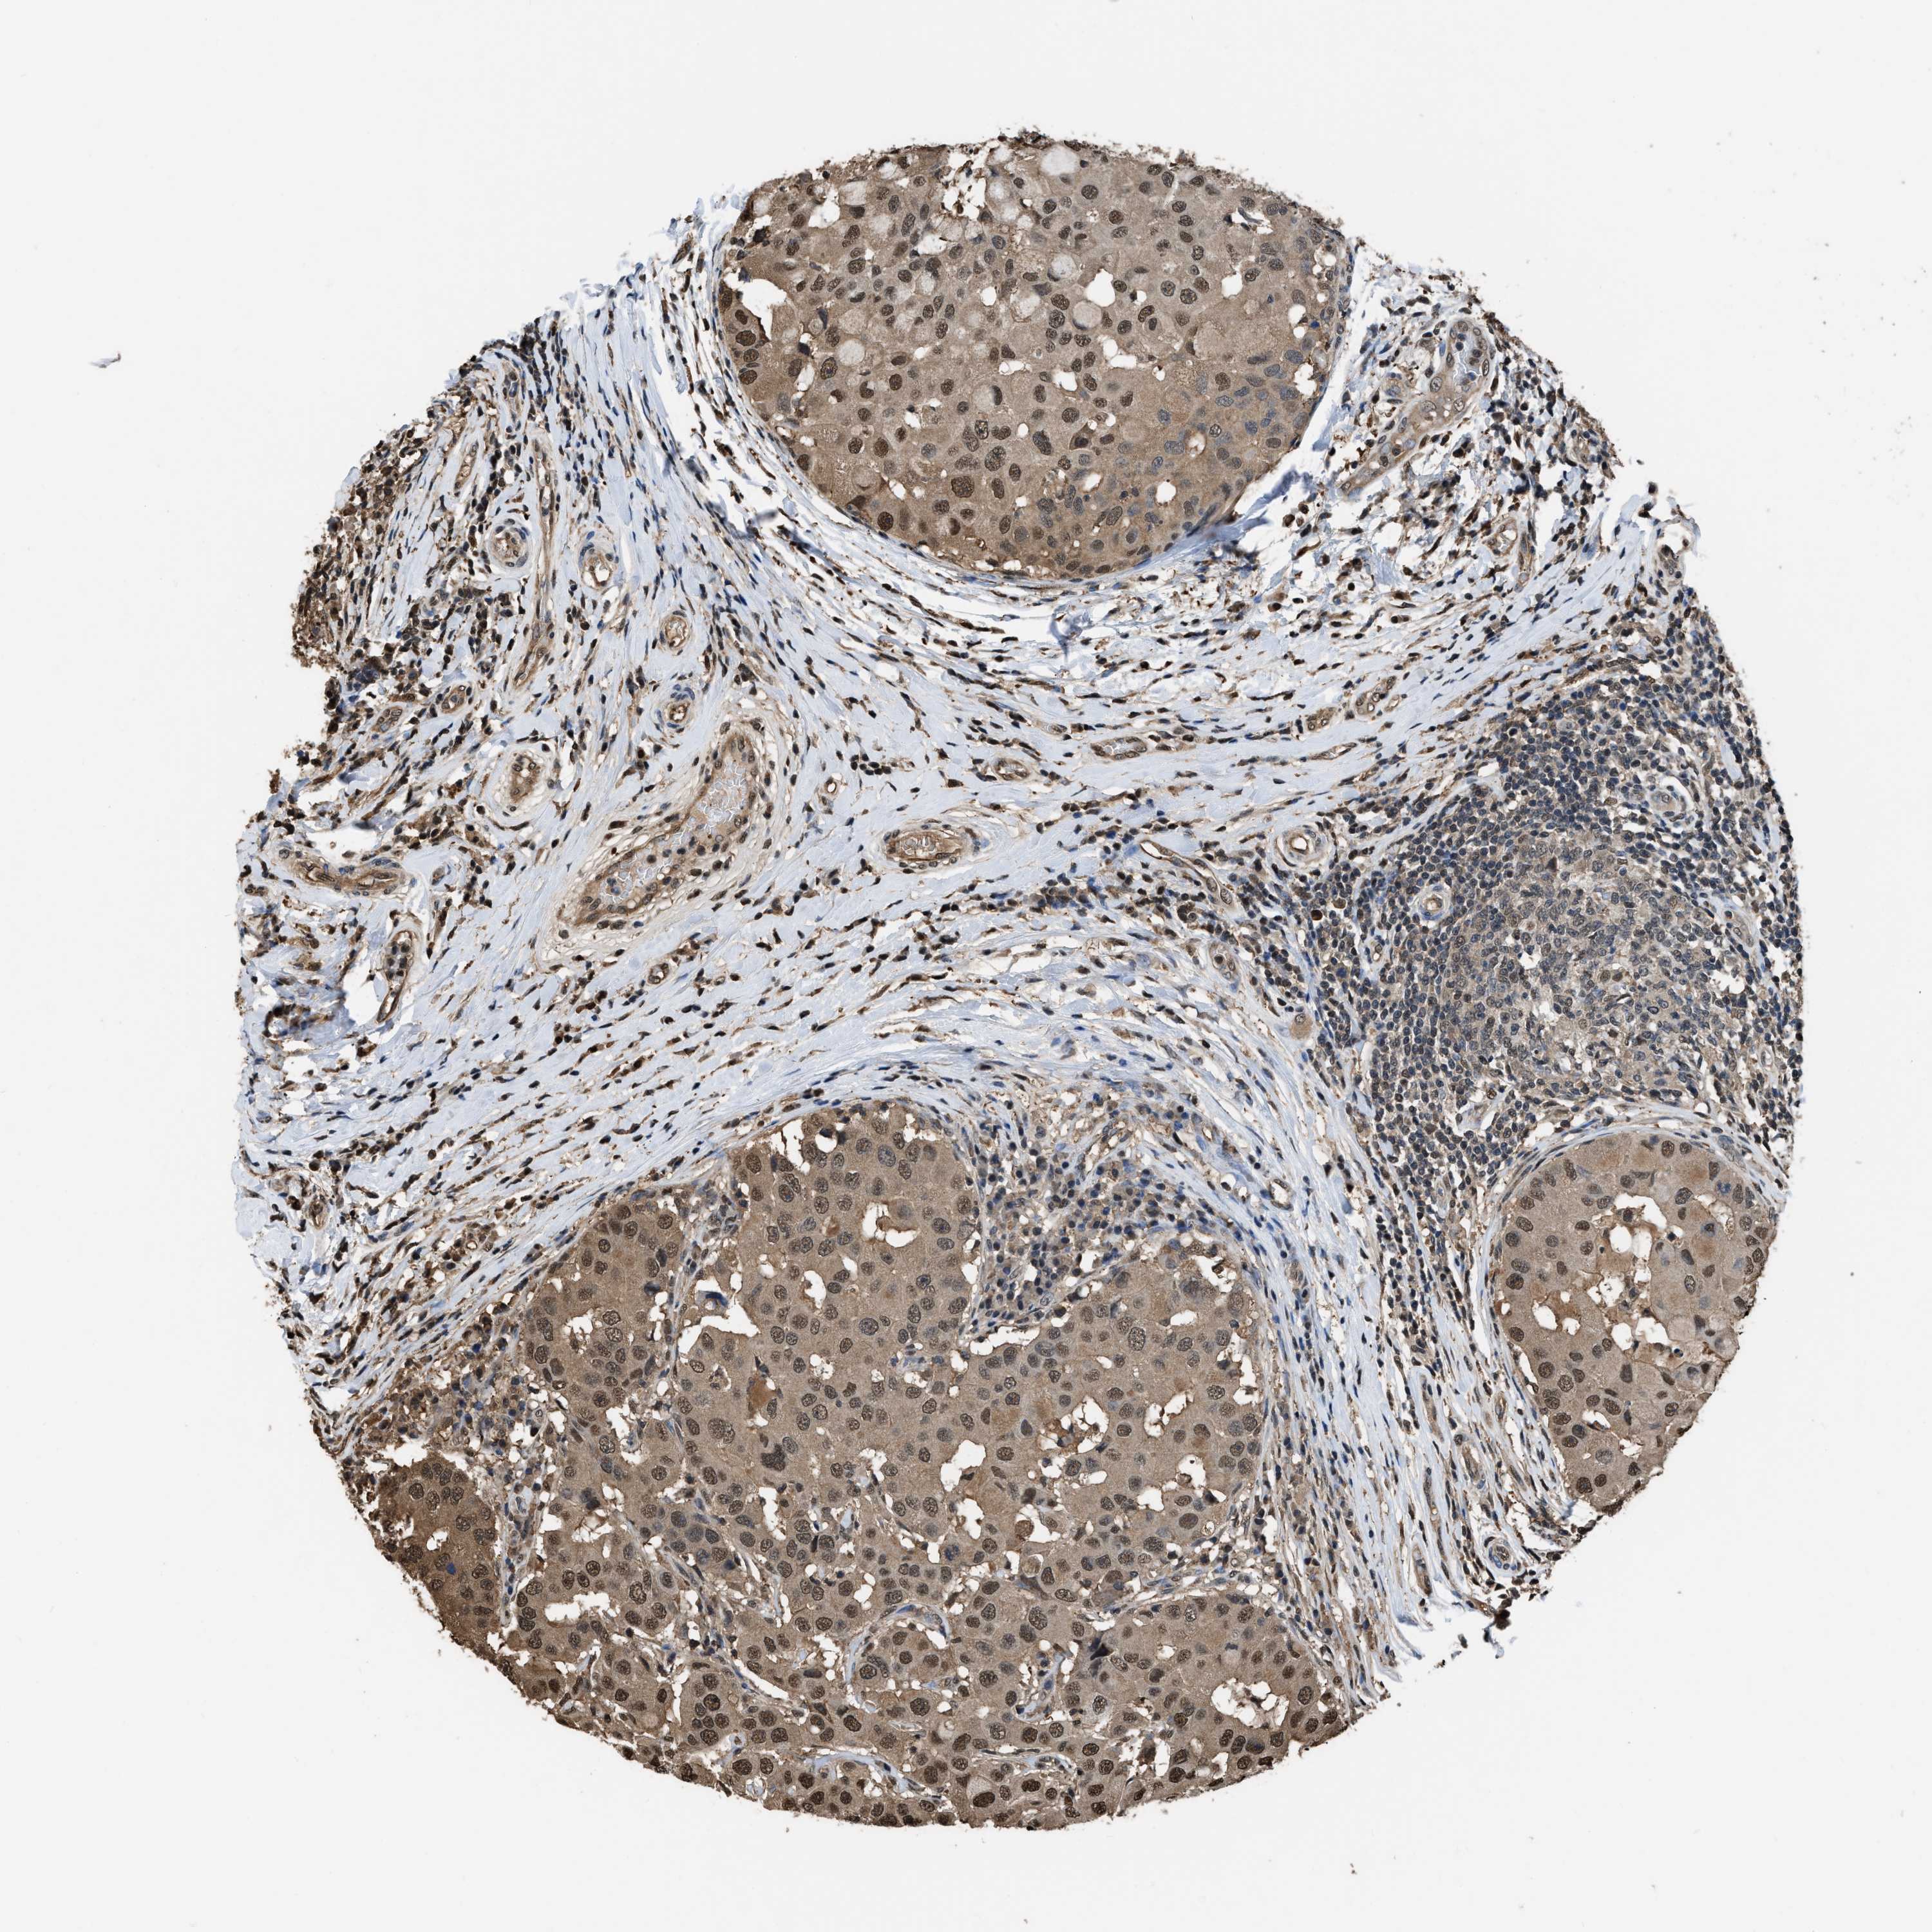

CANCER BREAST CANCER Show tissue menu

BRCA TCGA BRCA VALIDATION PROTEIN EXPRESSION

ANTIBODIES